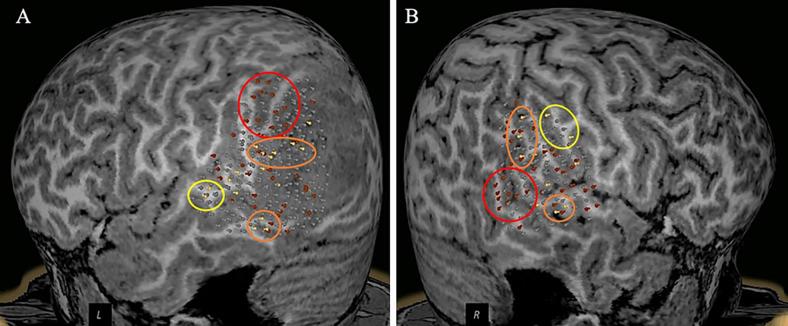

A 13-year-old bilingual male with glioblastoma multiforme involving the left parietal lobe and deep occipital white matter underwent preoperative language mapping using magnetic resonance imaging-guided TMS. Language-specific cortices were successfully identified in both hemispheres. TMS findings aided in discussing with the family the risks of postsurgical deficits of tumor resection; postoperatively, the patient had intact bilingual speech and was referred for chemotherapy and radiation.

一名13岁的双语男性患有多形性胶质母细胞瘤,累及左顶叶和枕叶深部白质,在磁共振成像引导下使用TMS进行了术前语言定位。在两个半球均成功识别出特定语言的皮质。TMS结果有助于与家属讨论肿瘤切除术后出现功能缺陷的风险;术后,患者的双语言语功能完好,并被转诊接受化疗和放疗。